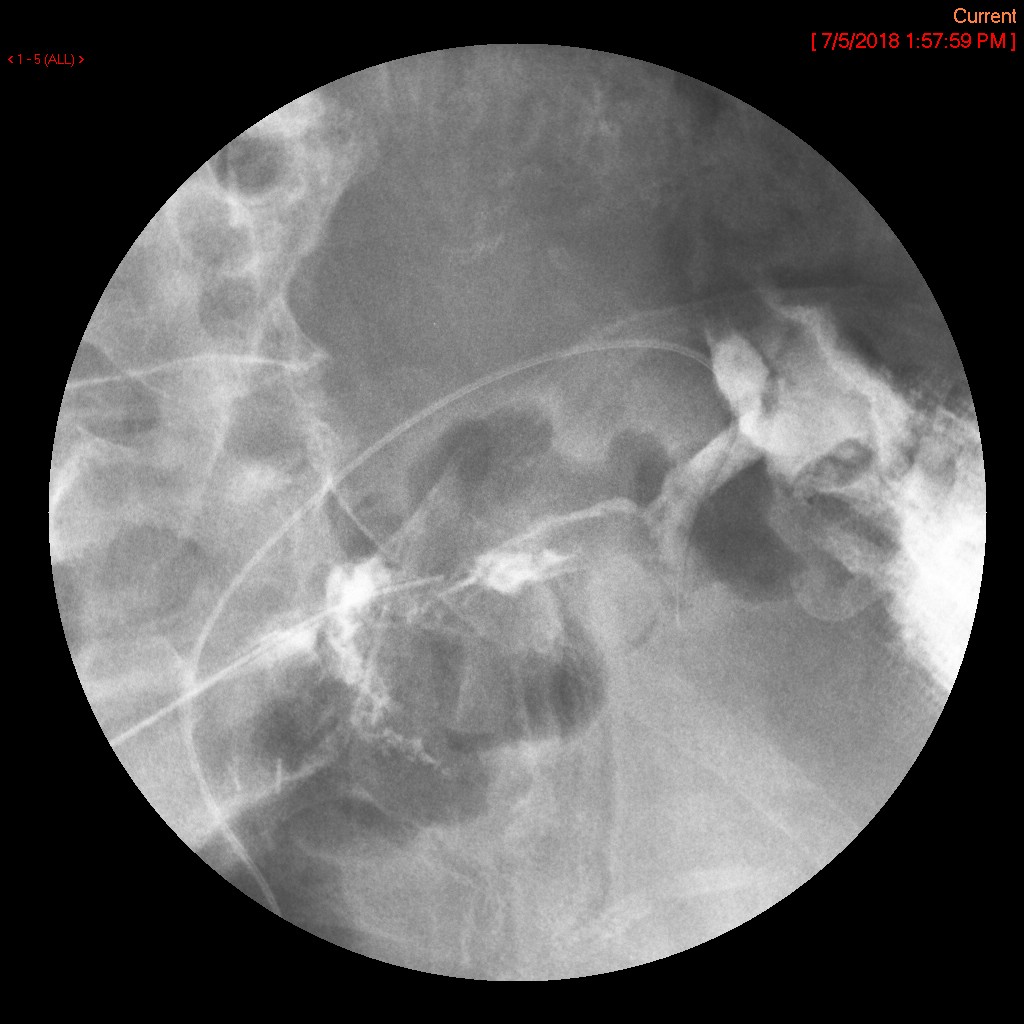

- Method:

- Upon entering the room, the patient will already be positioned supine on the fluoroscopy table. The interventional portion of the exam is performed by the Gynecology Department; the cervix should be cannulated and a catheter placed when you enter the room.

- Introduce yourself to the patient and the staff in the room.

- Move the fluoroscopy tower over the patient centering on the pelvis.

- The gynecologist will begin injecting contrast material into the uterus. Obtain images periodically throughout the procedure (usually at the direction of the gynecologist). The images should include the uterine cavity filled with contrast material, bilateral fallopian tubes filled with contrast material, and spillage and dispersion of contrast material into the peritoneal cavity (image 1) (image 2) (image 3) (image 4) (image 5).

- It may be necessary to place the patient into either the right lateral or left lateral oblique postion to define the anatomy more clearly.

- Spillage into the peritoneal cavity is not always seen. If this occurs during the examination, be sure to note it in the dictation.